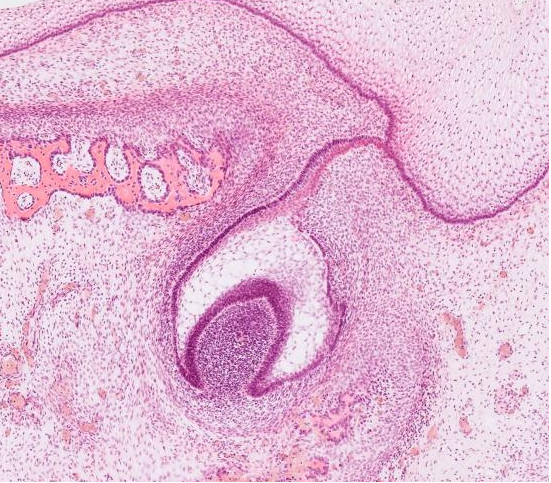

Глоточный аппарат и его производные. Особенности слизистой оболочки ротовой полости. Развитие и строение губы, языка, зуба. Лимфоидная ткань: строение небной миндалины. Малые слюнные железы

- Особенности строения слизистой оболочки тонкой кишки: ворсинки, крипты, эпителий, его клеточный состав. Различия в строении двенадцатиперстной, тощей, подвздошной кишки. Морфологическая характеристика толстой кишки, клеточный состав эпителия крипт. Лимфоидная ткань тонкой и толстой кишки.